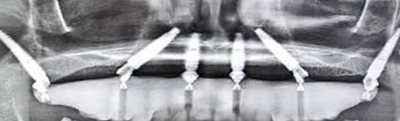

All on 6 dental implants represent a highly customized, biomechanically driven approach to full arch tooth replacement. By using six strategically placed implants, this treatment provides enhanced load distribution, long-term stability, and greater restorative flexibility—especially in complex cases or revision scenarios.

Six implants provide increased surface area, improved force distribution, and greater redundancy—important factors in long-term implant success.

Pterygoid implants anchor into dense bone behind the upper jaw, eliminating the need for sinus grafting in many upper-arch cases. These implants provide posterior support where bone is often lacking.

Transnasal implants engage dense nasal floor bone to stabilize upper arch restorations in patients with advanced bone loss. This technique is especially valuable in revision cases and complex maxillary anatomy.

Implants are placed using digitally guided surgical protocols for precision and safety.